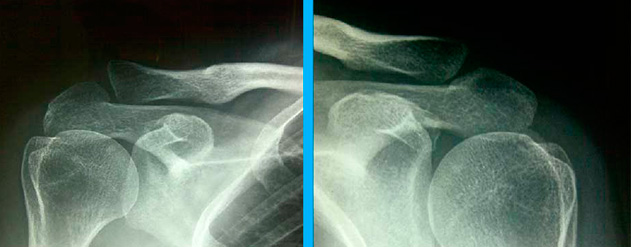

Ecografía después de 1 mes de haber terminado la terapia de Ondas de Choque (Imagen).